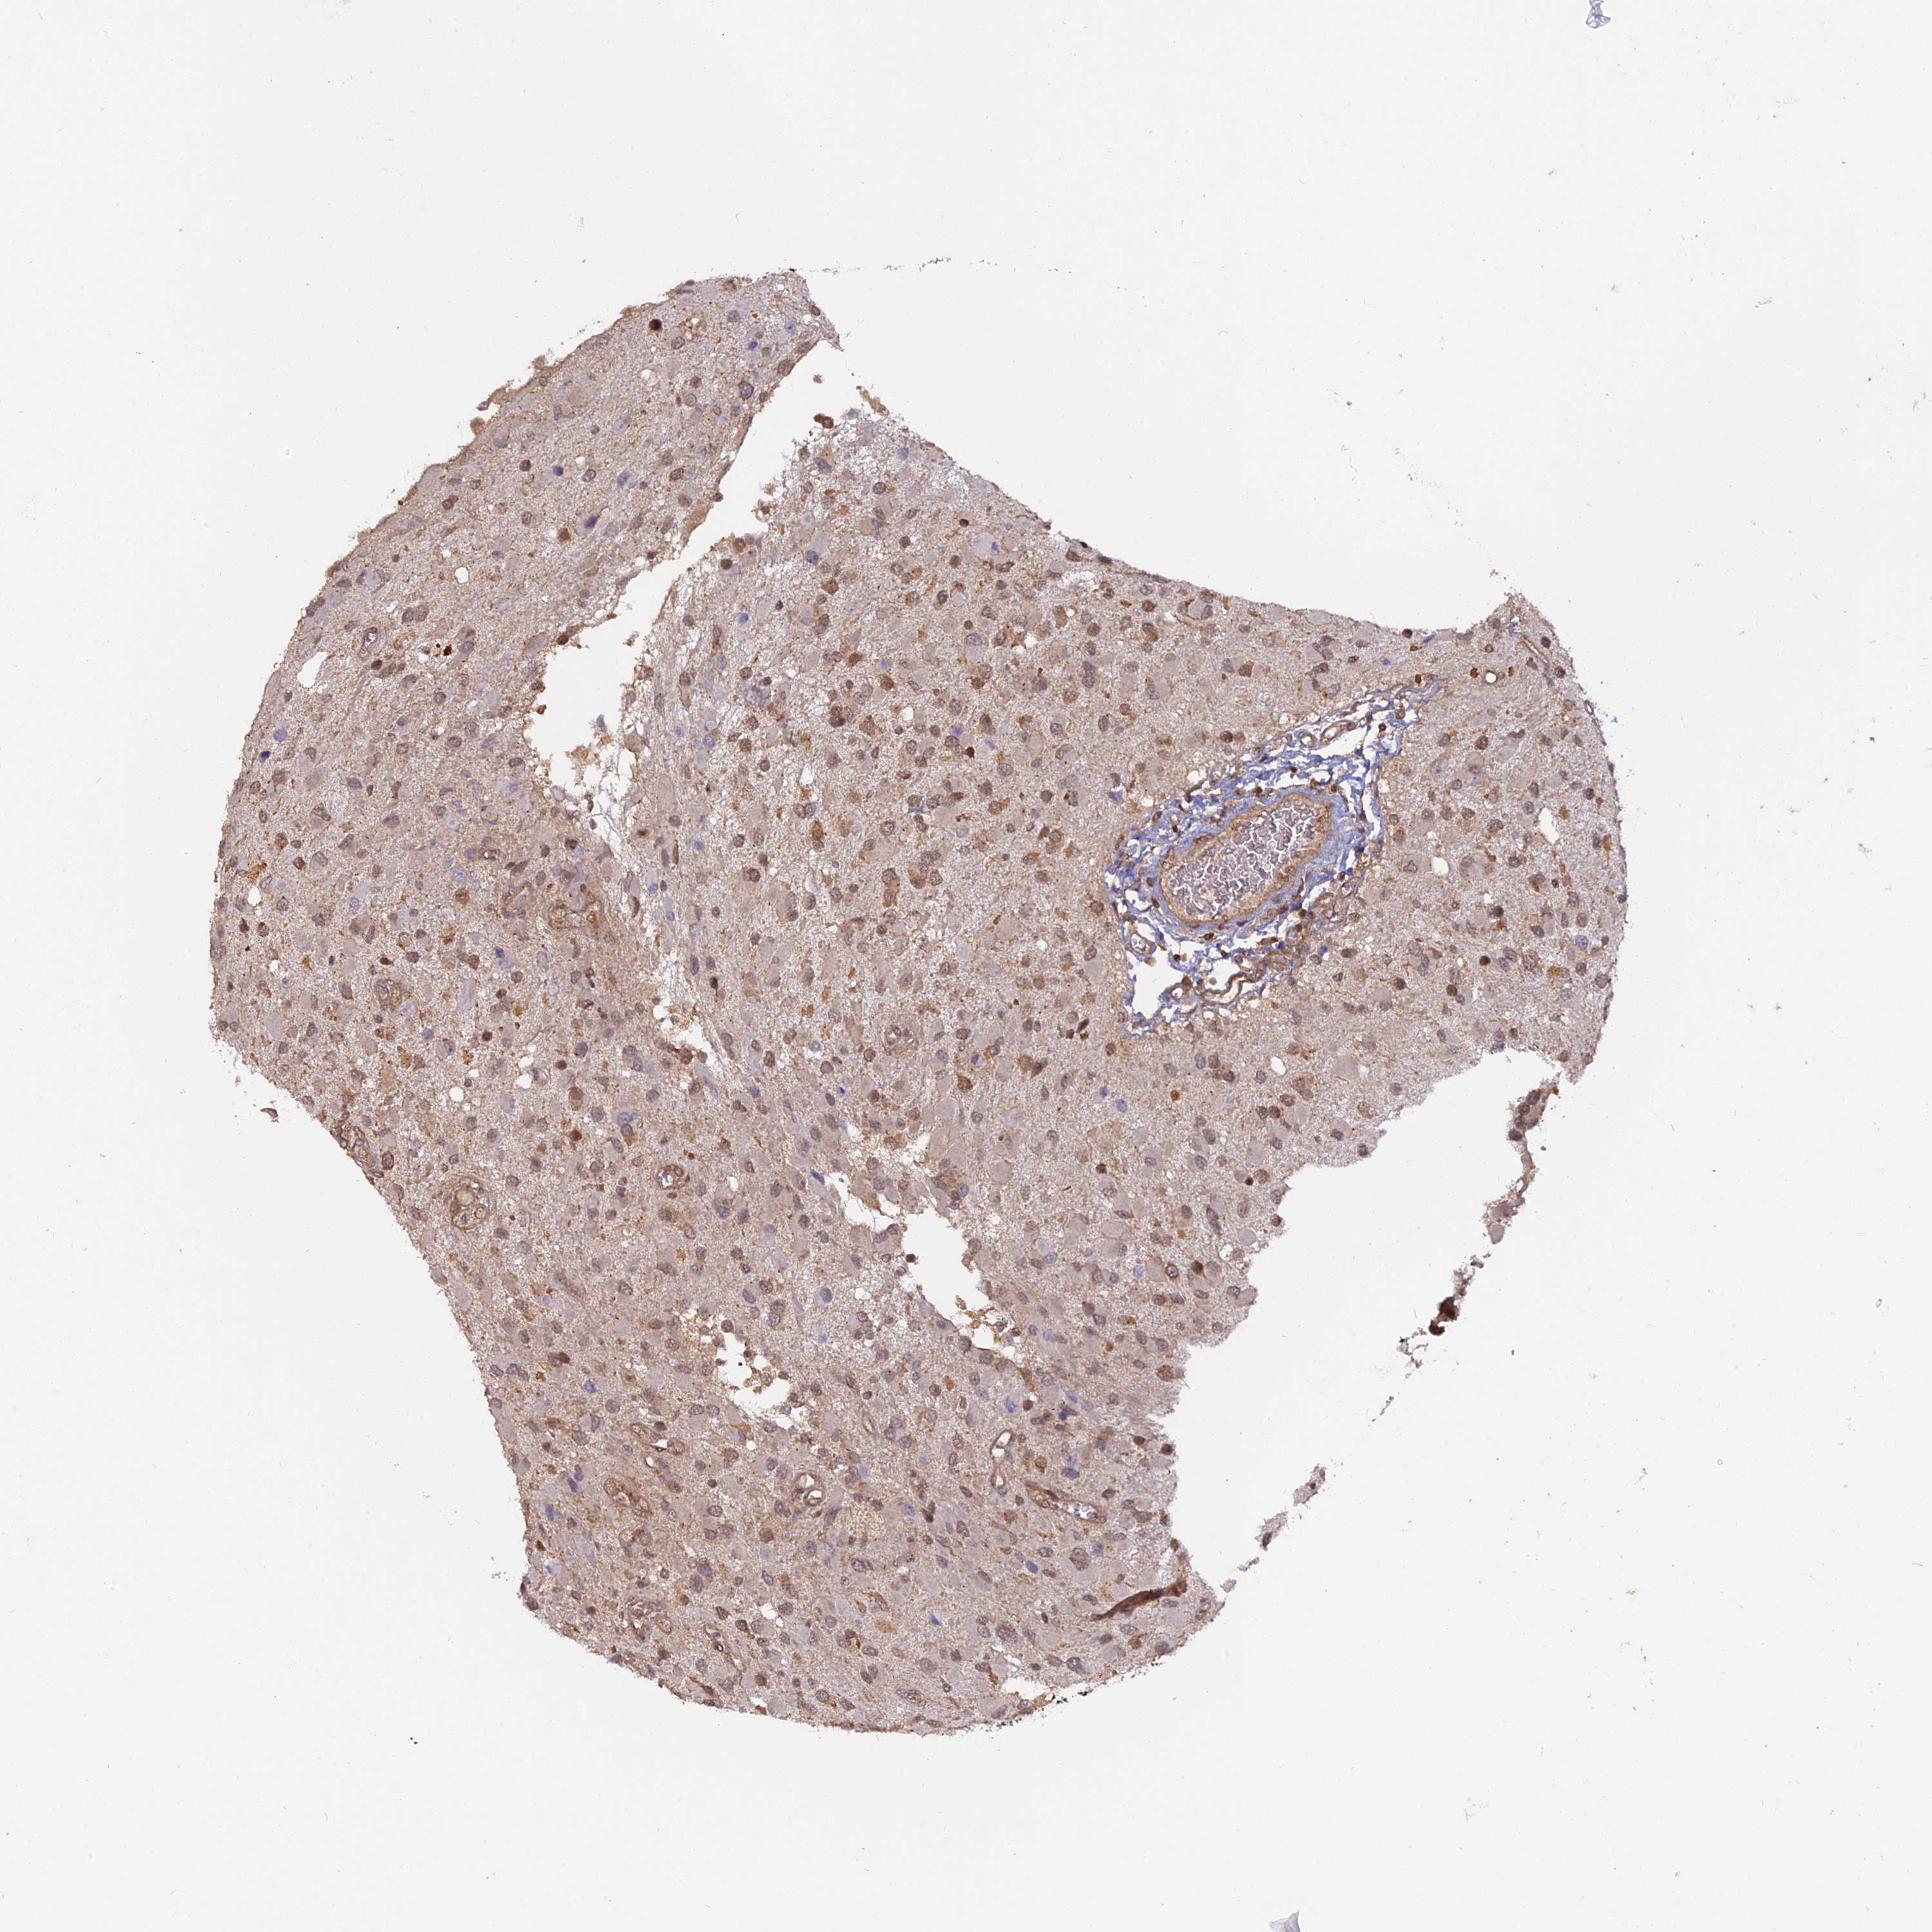

GLIOMA - Protein expressioni

A mouse-over function shows sample information and annotation data. Click on an image to view it in a full screen mode. Samples can be filtered based on level of antibody staining by selecting one or several of the following categories: high, medium, low and not detected. The assay and annotation is described here.

Note that samples used for immunohistochemistry by the Human Protein Atlas do not correspond to samples in the TCGA dataset.

Antibody stainingi

Antibody staining in the annotated cell types in the current human tissue is reported as not detected, low, medium, or high, based on conventional immunohistochemistry profiling in selected tissues. This score is based on the combination of the staining intensity and fraction of stained cells.

Each image is clickable and will lead to virtual microscopy that enables deeper exploration of all samples and also displays staining intensity scores, fraction scores and subcellular localization as well as patient and tissue information for each sample.

Antibody HPA042703

Staining

High

Medium

Low

Not detected

Intensity

Strong

Moderate

Weak

Negative

Quantity

>75%

75%-25%

<25%

None

Location

Nuclear

Cytoplasmic/membranous

Cytoplasmic/membranous,nuclear

Glioma, malignant, High grade

Glioma, malignant, Low grade